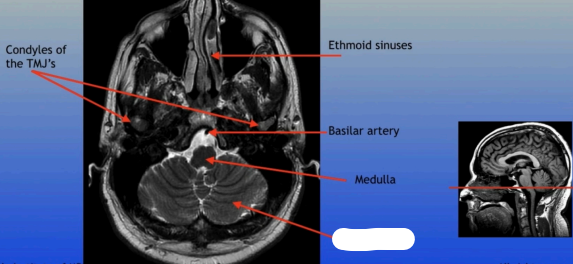

Condyles of the TMJ

Ethmoid Sinuses

Basilar Artery

Medulla

Cerebellum